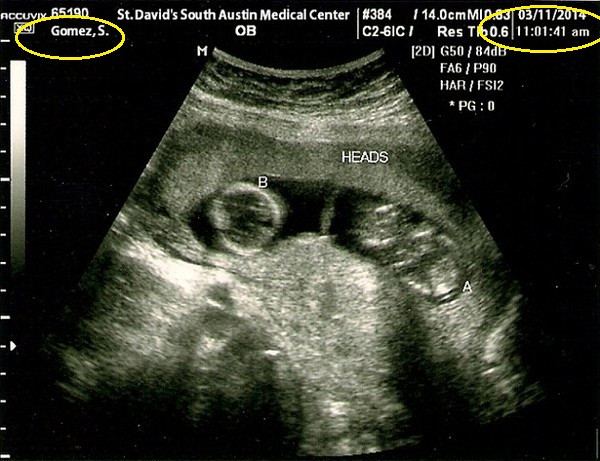

Vừa qua, một bức hình chụp siêu âm với tên bệnh nhân là “Gomez, S.” được đăng tải tràn lan trên mạng Internet và khẳng định rằng đó chính là ảnh siêu âm của nữ ca sĩ Selena Gomez đã khiến nhiều người rất bất ngờ.

Khi nhìn kỹ bức ảnh này có thể thấy rõ là có đến hai bào thai nên một số trang báo đã ngay lập tức lợi dụng để tung tin Selena mang thai song sinh với Justin Bieber.

Bên cạnh đó, trên bức ảnh này ghi thời gian được thực hiện là vào ngày 11/3/2014 tại Trung tâm y tế St.David's South Austin, ở Austin, Texas. Nhưng trong khoảng thời gian đó, Selena lại đang có mặt tại New York để chụp ảnh cho chiến dịch quảng cáo của một hãng thời trang nên chuyện đi siêu âm là không thể.

Trang HLife cũng vào cuộc tìm kiếm nguồn gốc của bức ảnh và phát hiện ra đây là ảnh đã được chỉnh sửa từ bức ảnh siêu âm của một phụ nữ tên Elle được thực hiện từ năm 2009.